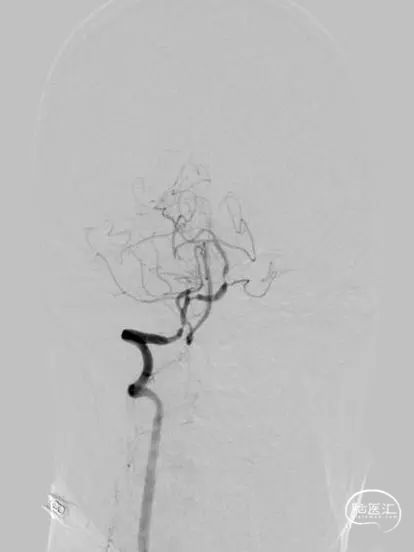

头颅核磁示:双侧小脑、双侧枕叶多发性脑梗死,部分趋于急性期。头颅磁共振MRA提示:双侧椎动脉V4重度狭窄;基底动脉上段轻度狭窄。

脑血管造影:主动脉弓+右侧颈总动脉造影。

左侧颈总动脉造影。

左侧锁骨下动脉造影。

右侧锁骨下动脉造影。

300cm微导丝携Gateway球囊到位,行球囊扩张及预扩张后造影。